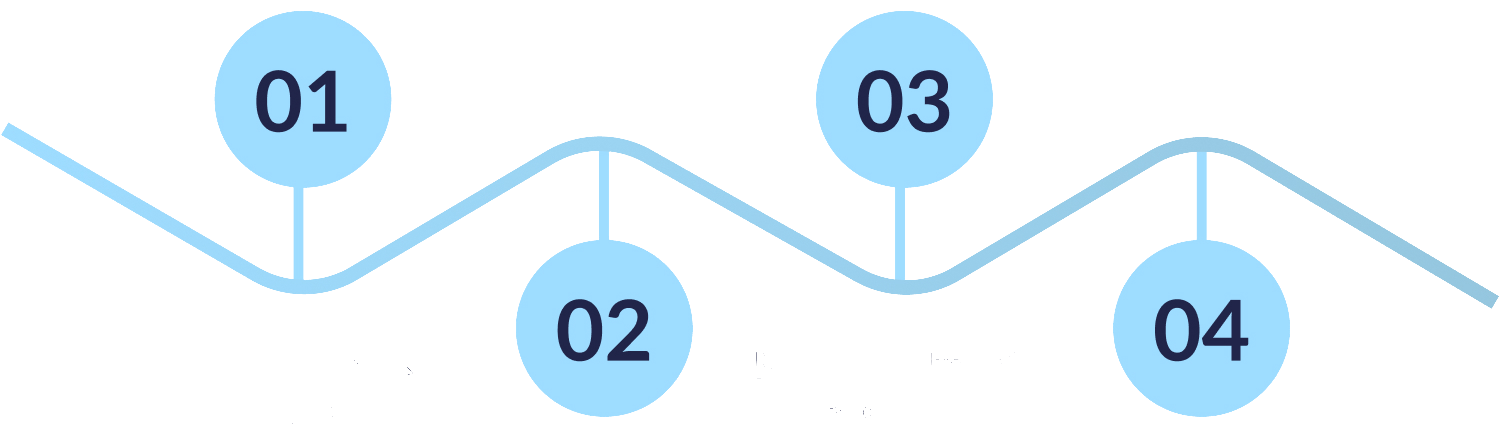

Review of medical history, exam, and MRI/ultrasound if needed.

Performed under local anesthesia, usually within minutes.

01Consultation & Imaging

Review of medical history, exam, and MRI/ultrasound if needed.

02Personalized Treatment Plan

Choice of injection, nerve block, or advanced procedure depending on the cause.

03Outpatient Procedure

Performed under local anesthesia, usually within minutes.

04Recovery & Follow-Up

Most patients return to walking and daily activities quickly, with ongoing support as needed.